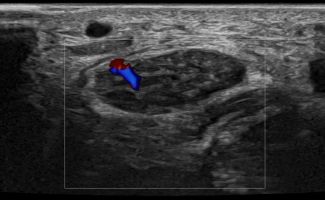

- Focal Lesions (tumors, neuromas)